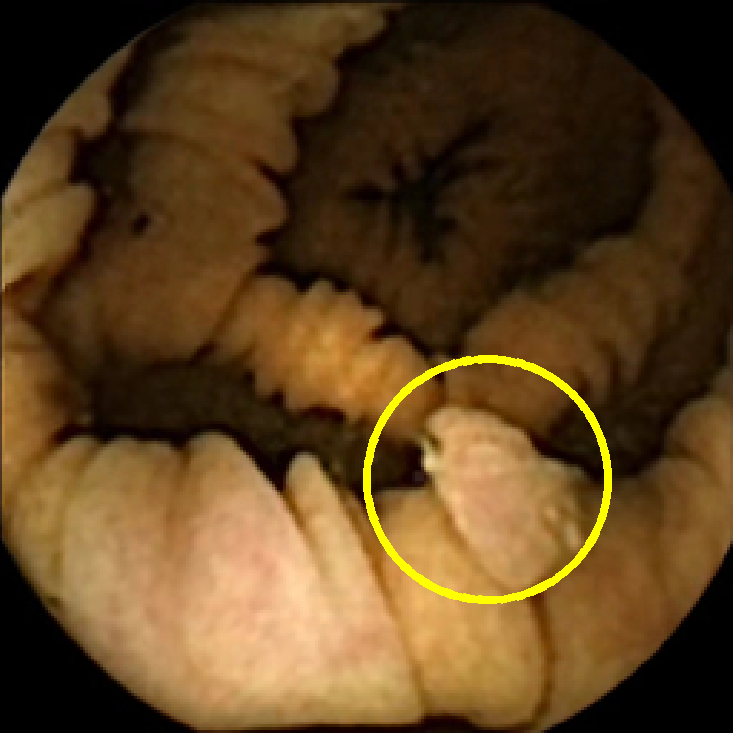

We illustrate the above considerations in Figure 4, where we compare the ellipses of inertia for a polyp frame and two frames with pronounced mucosal folds. The ellipses we plot are

| (20) |

where . The scaling term in front of is chosen so that the area of the ellipse of inertia is the same as the size of the corresponding feature.

As expected, we observe that the ellipses corresponding to mucosal folds (feature 2 in the second row and features 2 and 3 in the third row of Figure 4) are indeed much more stretched out than the ellipse corresponding to a polyp (feature 1 in the first row of Figure 4). Stretched ellipses imply higher eccentricity, thus we impose the following criterion

| (21) |

with some threshold to select moderately stretched features that are more likely to correspond to polyps.